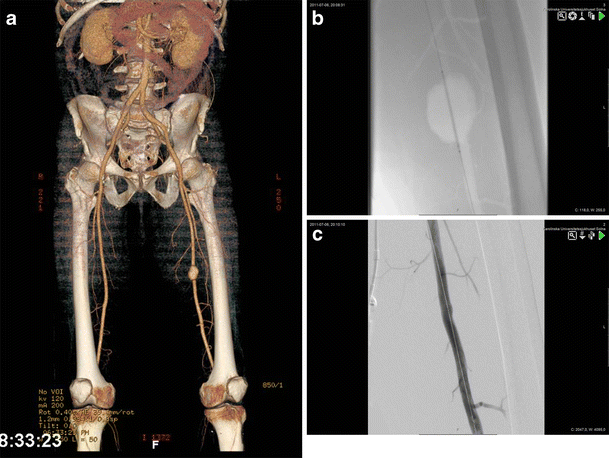

Stabbed superficial femoral artery repaired with venous interposition graft